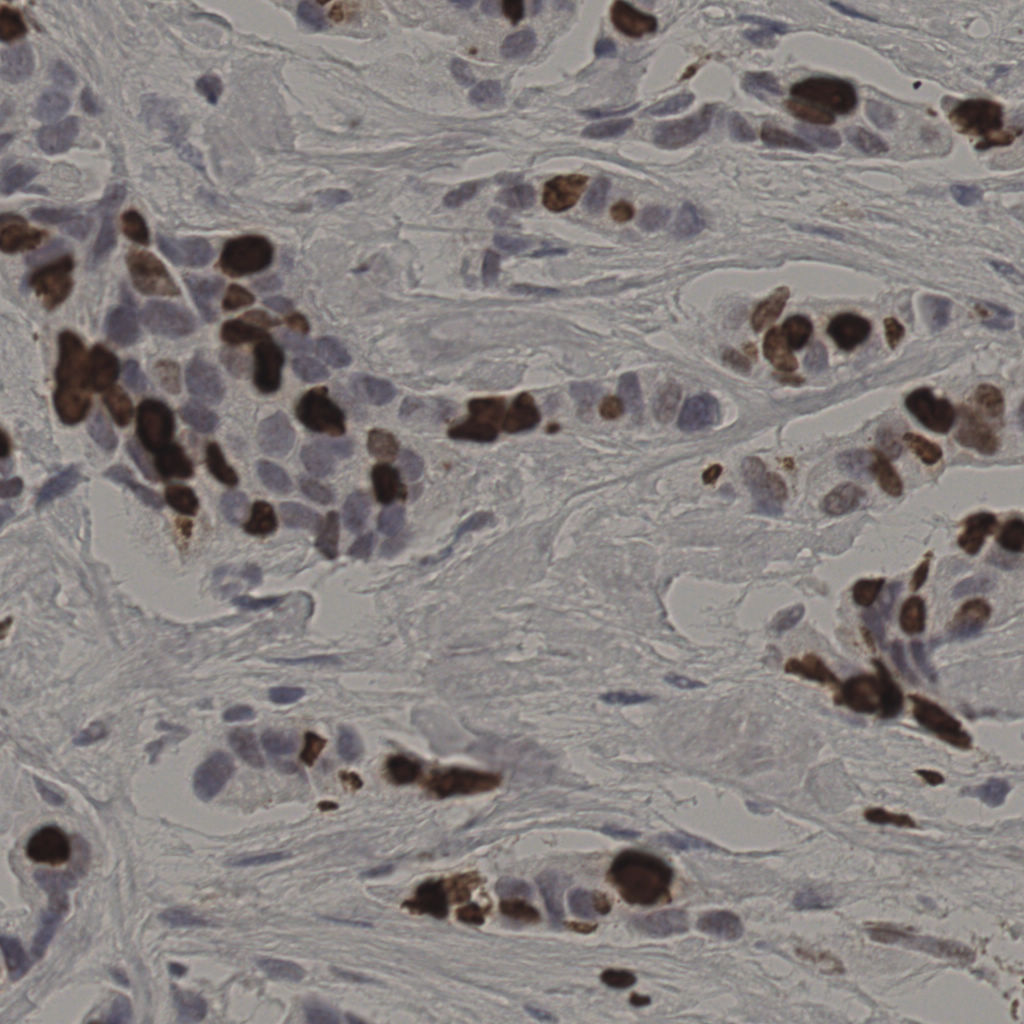

17.75%

Ki67 指数

阴 7986

阳 1723

切片统计

总切片

2640

有效

412

已标记

412

有效率

16%